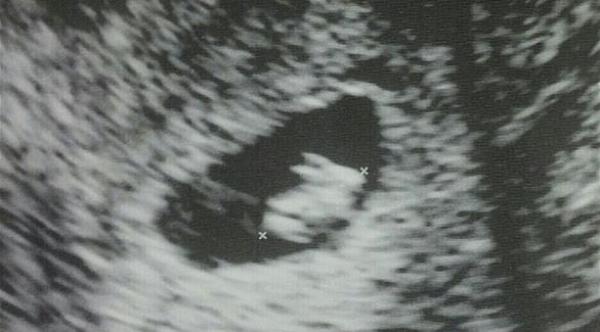

وتوضح الصورة التي نُشرت على الشبكة الاجتماعية جنين على هيئة "أرنب" صغير بأذنين وأربعة أقدام، وبغض النظر عما إذا كانت الصورة حقيقية أم وهمية، إلا أنها أثارت مستخدمي الشبكة وانتشرت على الإنترنت وجذبت العديد من التعليقات الساخرة.

وكتبت صاحبة المنشور التي تقطن في فلوريدا أسفل الصورة "هذه صورة الموجات فوق الصوتية التي التقطت اليوم لجنيني في الأسبوع السابع، فقد تبين أنني حامل في أرنب...أعتقد أنه أمر مضحك"، بحسب صحيفة دايلي ميل البريطانية.